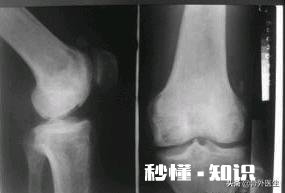

文章插图

解剖显示:关节软骨是位于关节腔内两关节面之间,膝关节软骨呈半月状,故有“半月板”之称 。而半月板的生理特点之一就是不可再生性 。所以机体各部位软骨的保护,永远大于患病后的修复 。